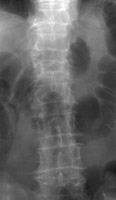

- Click on the image for a larger versionBAP radiograph of the lumbar spine. This shows loss of height of the L1 vertebral body, corresponding to a compression fracture.